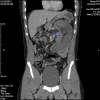

Abdominal pain secondary to intussusception is a common presentation in the paediatric population but rare in adults. Diagnosis is often difficult due to non-specific signs and symptoms. Adult intussusception presents more insidiously with intermittent abdominal pain and signs and symptoms of an acute abdomen are rare. In children, the aetiological factor is usually idiopathic, whereas intussusception in adults is more commonly due to an underlying pathology giving rise to a lead point. Consequently the treatment of choice is different-while it is supportive in children, surgical management is typically indicated in adults. In addition, the causes of a lead point precipitating adult intussusception are different depending on whether they arise from the small or large bowel. This report presents a case of jejunal intussusception in a 30-year-old man with a characteristic CT scan who required exploratory laparotomy and small bowel resection.